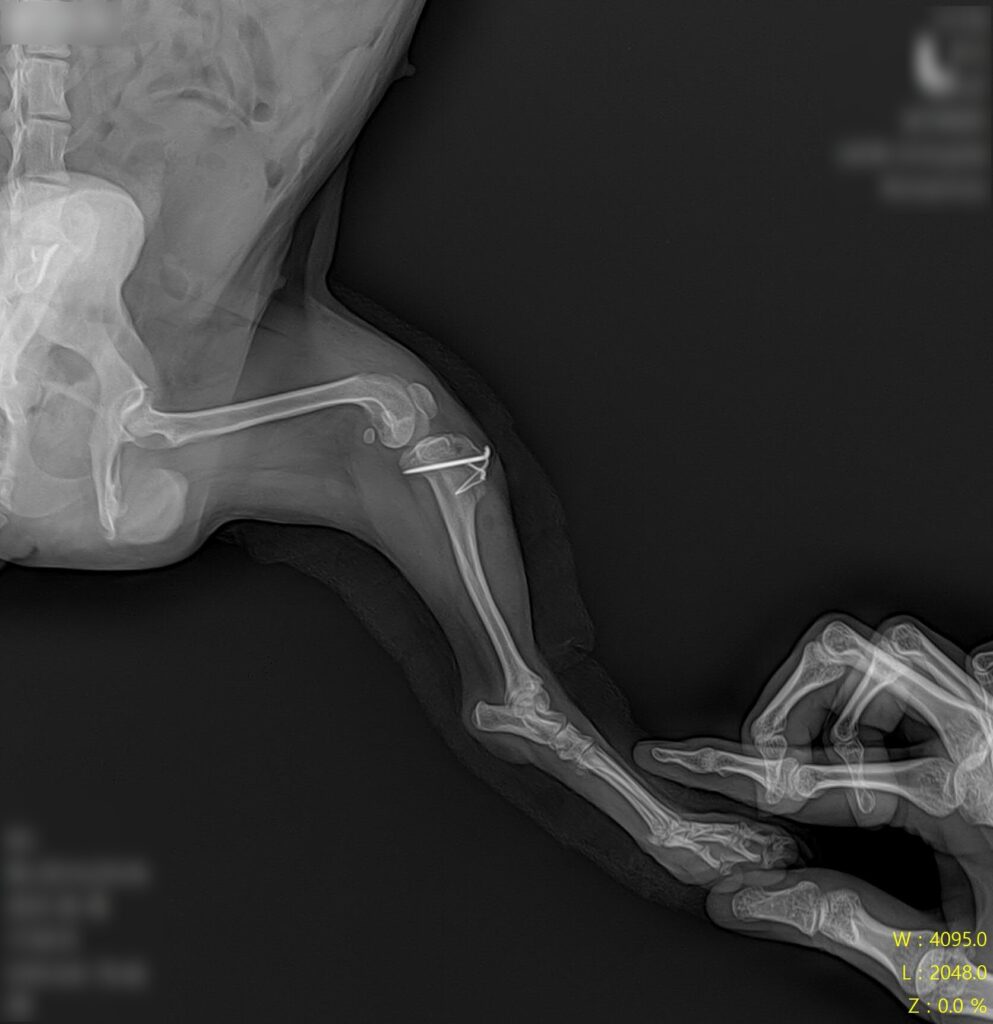

마취 전 방사선 검사 / 출처: 라온동물메디컬센터

정형학적 검사와 방사선 영상 검사를 진행한 결과, 슬개골탈구 4기(말기, terminal) 소견이 확인되었습니다. 슬개골이 완전히 고정 탈구된 상태였고, 활차구의 심각한 평탄화와 경골 조면의 내측 편위, 다리뼈의 비틀림이 동반되어 있었습니다.

2년 전 3기 진단 당시와 비교하면 그 사이 조용히, 그러나 빠르게 진행된 것이었어요. 보행이 크게 불편해 보이지 않았던 이유는 강아지가 변형된 뼈 구조에 스스로 적응하며 걷고 있었기 때문입니다.